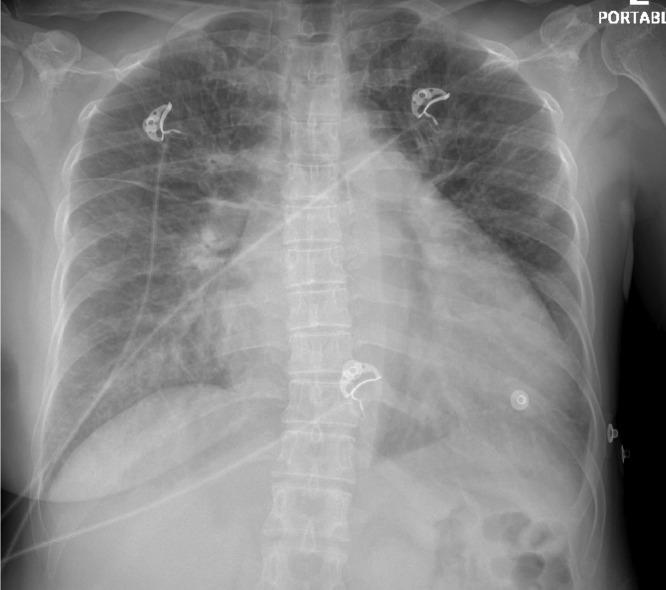

Heart failure (HF) is a clinical syndrome with a wide spectrum of presentations and an even wider array of etiologies. Anthracyclines such as Doxorubicin, Daunorubicin, Idarubicin, and Epirubicin have demonstrated increased risk of HF with significant morbidity and mortality. We present an interesting case report of a patient with a history of breast cancer treated with Doxorubicin who presented with symptoms of HF who had a comprehensive evaluation that excluded the most common etiologies, narrowing our diagnosis to late onset doxorubicin induced HF with on-going recovery after initiation of guideline-directed medical therapy.

心力衰竭(HF)是一种临床表现多样、病因更为广泛的临床综合征。阿霉素、柔红霉素、伊达比星和表柔比星等蒽环类药物已显示出发生HF的风险增加,且具有显著的发病率和死亡率。我们报告了一例有趣的病例,该患者有乳腺癌病史,曾接受阿霉素治疗,出现了HF症状,经过全面评估排除了最常见的病因,将诊断范围缩小为迟发性阿霉素诱导的HF,在开始指南指导的药物治疗后病情正在恢复。